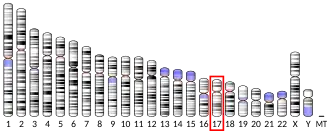

ERBB2, a known proto-oncogene,[11] is located at the long arm of human chromosome 17 (17q12).[12]